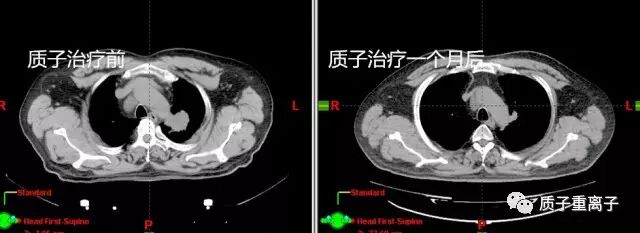

质子治疗一个月后复查:肿瘤较前明显缩小

质子治疗一个月前后对比:肿瘤由治疗前最大截面3.9×3.88cm缩小为2.13×2.48cm,治疗前肿瘤体积为44.56cm3,治疗一个月后为15.68cm3,体积缩小65%;